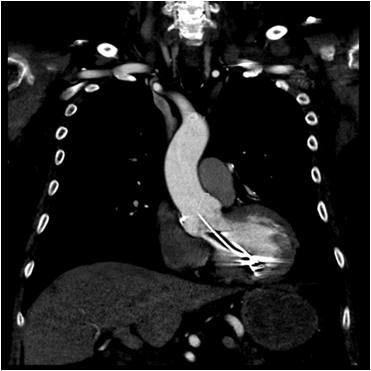

The next morning, the patient was noted to have a change in his neurological exam. He developed dysarthria and ataxia. A stat CT of the head was ordered and showed a new hypodensity within the left cerebellum and chronic periventricular small vessel ischemic changes. An MRI of the brain showed areas of acute infarction in the left parietal lobe, left occipital lobe and left cerebellum with small areas of hemorrhagic transformation in the left parietal lobe infarct. A subsequent MRA of the neck with Intravenous contrast showed a hypointensity in the visualized left subclavian artery which could represent a contrast mixing artifact or thrombus. The stroke was thought to be embolic in nature given the multiple territories involved. Given the MRA findings, a stat CTA of the neck and chest was done for further evaluation. The imaging studies showed the left ICD lead located in the left subclavian artery extending into the aorta and into the left ventricle of the heart. The patient was started on a heparin drip with the plan being to retrieve the ICD lead intraoperatively. Under general anesthesia, the patient underwent a left brachial artery cut down with subsequent removal of the defibrillator generator and lead retraction into the subclavian artery and placing a sheath into the artery. An angiogram was performed which showed that the subclavian artery was patent, and the left internal mammary artery (LIMA) and vertebral arteries were visualized indicating there was no evidence of active extravasation or pseudoaneurysm. In addition, there was no evidence of an arteriovenous (AV) fistula. A new AICD was placed and a subsequent angiogram obtained showed no bleeding. The artery was then repaired with good Doppler signal afterward. The patient was hemodynamically stable throughout the procedure and a post-procedure chest X-ray showed a single lead AICD overlying the right ventricle. The patient’s neurological status improved and the patient was subsequently discharged 2 days later to a rehab facility (Figure 1-3).

Management of inadvertent left ventricle lead placement is not well defined. If diagnosed immediately, it is recommended to remove the lead to avoid future thromboembolic complication. Serious complications with percutaneous lead extraction can happen including fatal hemorrhage, pseudoaneurysm formation, arterial dissection or occlusion, and distal embolism.13 Sheaths that are advanced over the lead may dislodge thrombi and cause systemic emboli.7 Our patient was on heparin drip during the procedure and fortunately, the lead extraction was uneventful. Treatment of malpositioned lead in the left heart diagnosed late includes anticoagulant therapy or lead removal. Lead extraction can be considered and is most appropriate if cardiac surgery has to be performed for other indications. If the malpositioned lead in the left ventricle is not extracted, then lifelong anticoagulant therapy needs to be commenced. Warfarin seems to be effective in primary and secondary prevention of thromboembolic events as antiplatelet therapy as thromboembolism prophylaxis is not recommended.7 The role of direct oral anticoagulants (DOAD) in these patients is not known (Figure 4 & Figure 5).

Figure 4 CTA of the neck with IV contrast showing the AICD lead within the aorta.

Figure 5 CT of the chest with IV contrast showing the AICD lead within the left ventricle.